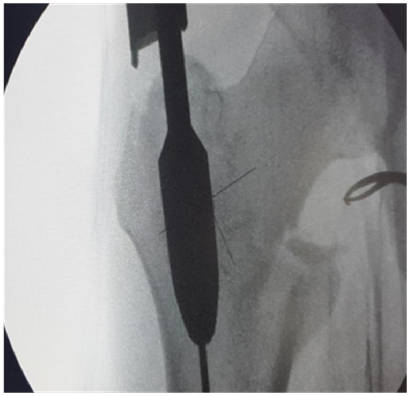

Failure of closed reduction

1. If there is failure of closed reduction better to open the fracture and achieve reduction by bone spikes/reduction clamp/ circlage wire etc.

2. Nail will not ensure reduction.

3. If reduction is not there the head screws will go into malposition (Figure 7).

Figure 7 Failure of closed reduction.